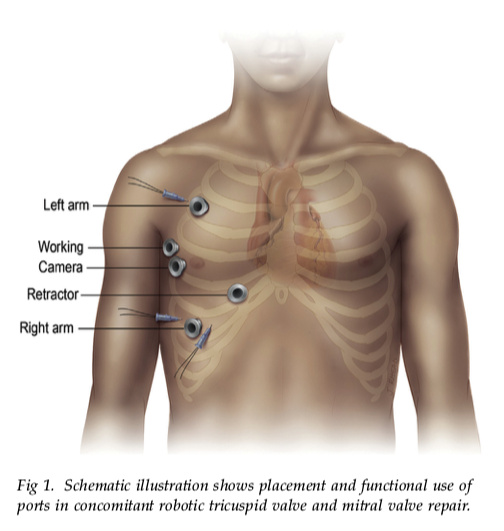

Robotic Cardiac Surgery: State of the Art in 2014 - part I - video

Robotic Cardiac Surgery: State of the Art in 2014 - part II - video

500th Robotic Cardiac Surgery at U. Chicago - video - 2017

Robot-assisted aortic valve surgery: State of the art and challenges for the future - International Journal of Medical Robotics - review - 2018